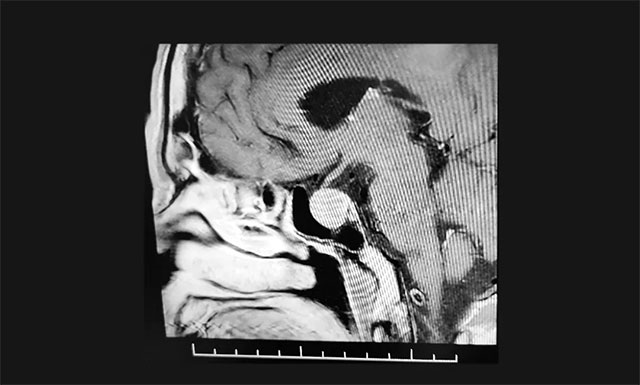

▲ 影像检查显示:垂体大腺瘤,超蝶鞍生长

鞍区MRI增强提示:蝶鞍显著扩大,鞍区(偏左侧)见一实性肿块影,超蝶鞍生长,左侧肿块矢橫高径约1.8*1.5*1.8cm。病变向鞍上生长,突入鞍上池,轻度推移视神经左侧份。鞍底受压变薄下陷,左侧鞍旁海绵窦受侵、外移,血管(颈内A)包绕约1/3以上。